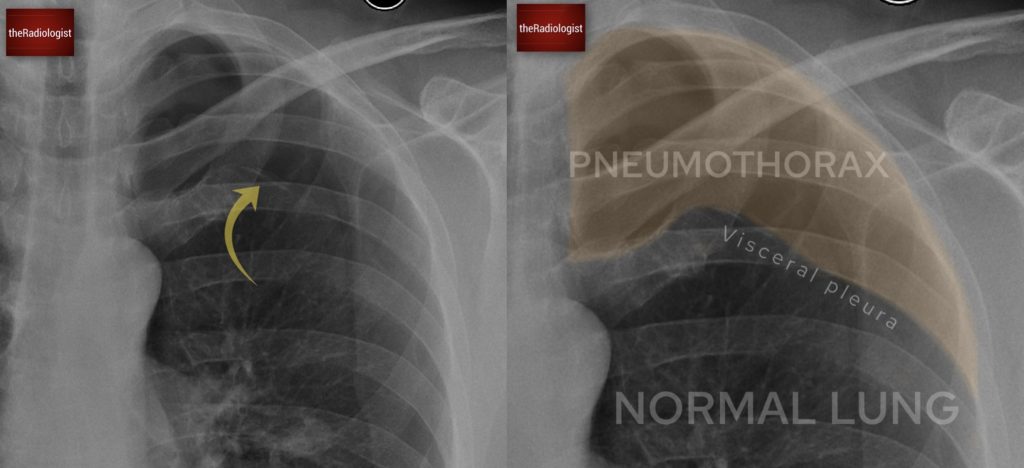

Here we have a PA chest X-ray with a lot going on. Did you notice the right-sided pneumothorax?

A pneumothorax occurs when air enters the pleural space which is the gap between the visceral and parietal pleura.

In a pneumothorax we find gas between the two layers of the pleura, the visceral and parietal pleura.

2. A thin white pleural line, representing the visceral pleura, with no lung markings beyond it.

In most cases gas will rise to the lung apex and the white pleural line will parallel the chest wall although there are exceptions. Sometimes a pneumothorax can be loculated and seen within the mid and lower zone whilst if an X-Ray is performed supine you may get  a ‘deep sulcus sign’ where there is a deepened costophrenic angle which is lucent.

Have a look at this separate case where we can see a white ‘pleural line’ representing the visceral pleura and gas within the pleural space.

In this separate case we can see a thin white pleural line representing the visceral pleura with no lung markings beyond it. This is typical for an apical pneumothorax. If you don’t zoom up you may miss this!